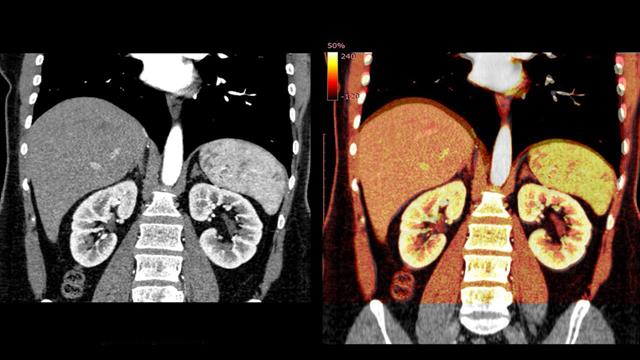

Τα ποδοκύτταρα αποτελούν σημαντικό συστατικό του λεγόμενου φραγμού αίματος-ουρίας. Στα περίπου ένα εκατομμύριο σπειράματα των νεφρών, καλύπτουν την επιφάνεια των αιμοφόρων αγγείων με τα "ποδαράκια" τους και λειτουργούν ως φίλτρο που επιτρέπει τη διέλευση μόνο ορισμένων ουσιών με χαμηλό μοριακό βάρος (οι πρωτεΐνες γενικά δεν περιλαμβάνονται).

Τα ελαττώματα έχουν ως αποτέλεσμα νεφριτικό σύνδρομο με οίδημα.

Είναι ήδη γνωστές διάφορες δυσλειτουργίες των ποδοκυττάρων που μπορούν να διαταράξουν τη λειτουργία του φίλτρου. Μια προηγουμένως υποτιμημένη αιτία αυτών των ποδοκυτταροπαθειών θα μπορούσε να είναι τα αυτοαντισώματα έναντι της πρωτεΐνης νεφρίνης.